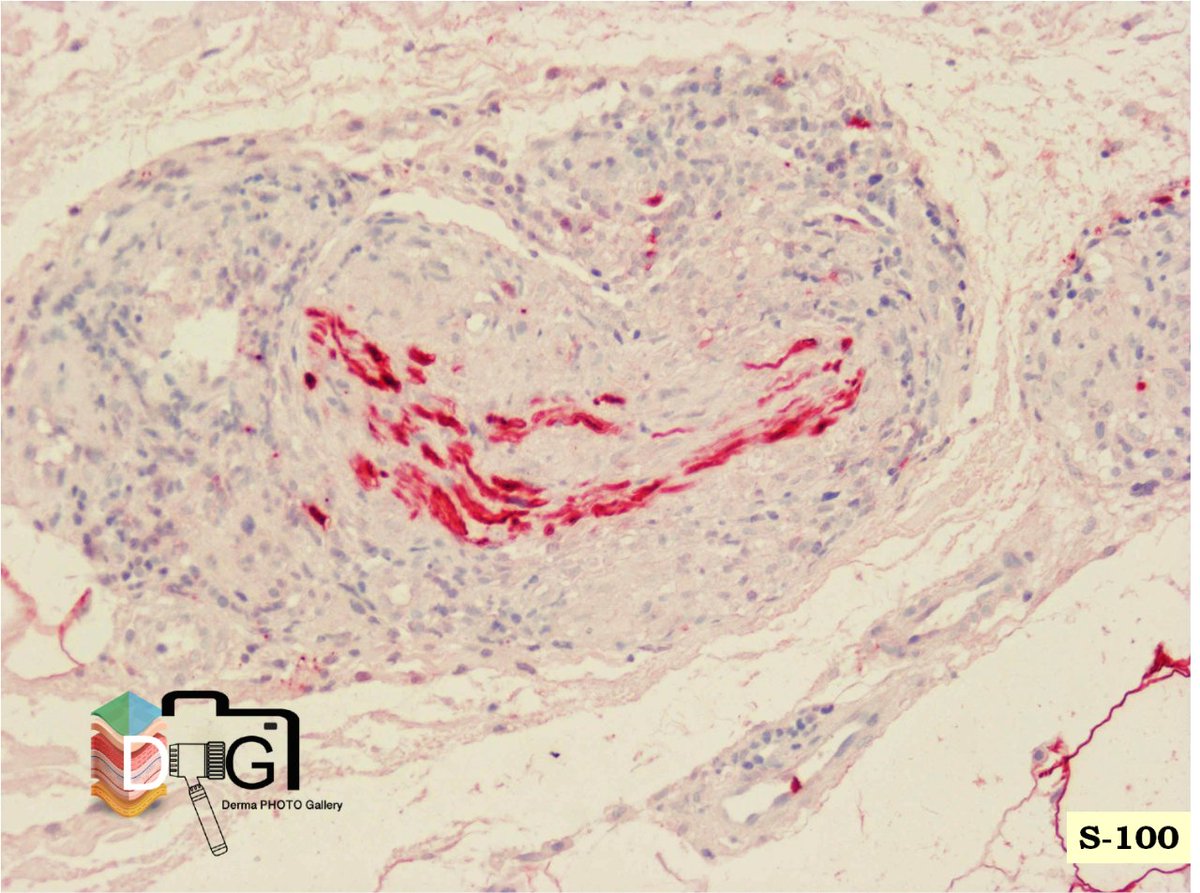

HISTOPATOLOGIA E INMUNOLOGIA DE LA LEPRA VII. 1/4

LEPRA TUBERCULOIDE SUBPOLAR (TTs). 1/2

Granulomas con signos activación epitelioide y menor circunscripción

Células gigantes tipo Langhans

Linfocitos con distribución + difusa respecto a macrófagos

Borramiento de la banda de Unna ImageImage

HISTOPATOLOGIA E INMUNOLOGIA DE LA LEPRA VII. 2/4

LEPRA TUBERCULOIDE SUBPOLAR (TTs). 2/2

Infiltrados liquenoides. Posible erosión epidérmica

Lesión neural importante

Los macrófagos de la lepra tuberculoide no expresan S-100

Marcada hiperplasia de células de Langerhans ImageImage